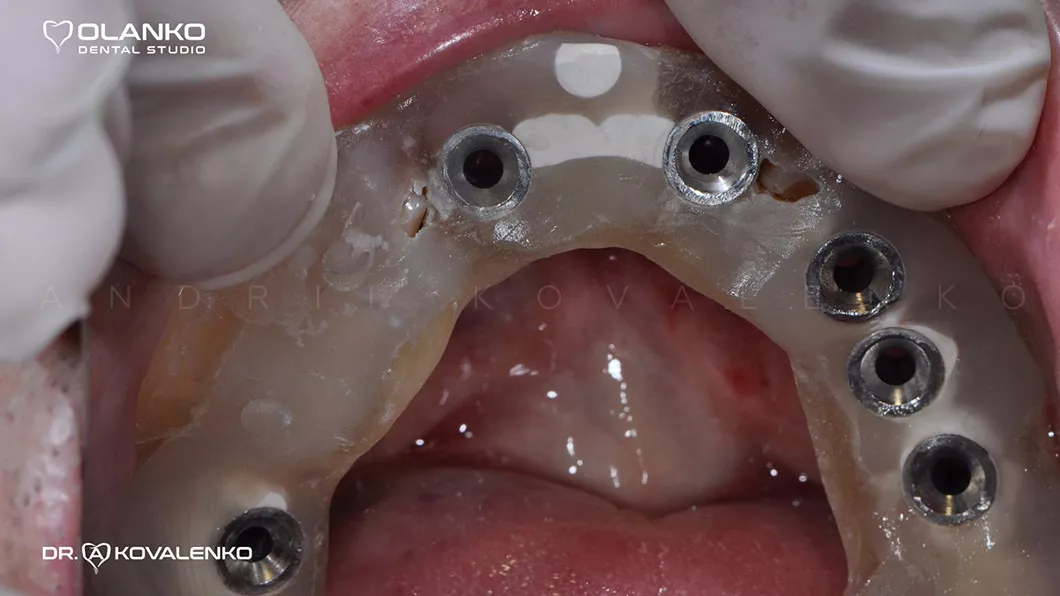

Установка имплантатов по шаблону

Вид в полости рта перед установкой керамических конструкций на имплантатах

Клинический случай 1 имплантация зубов